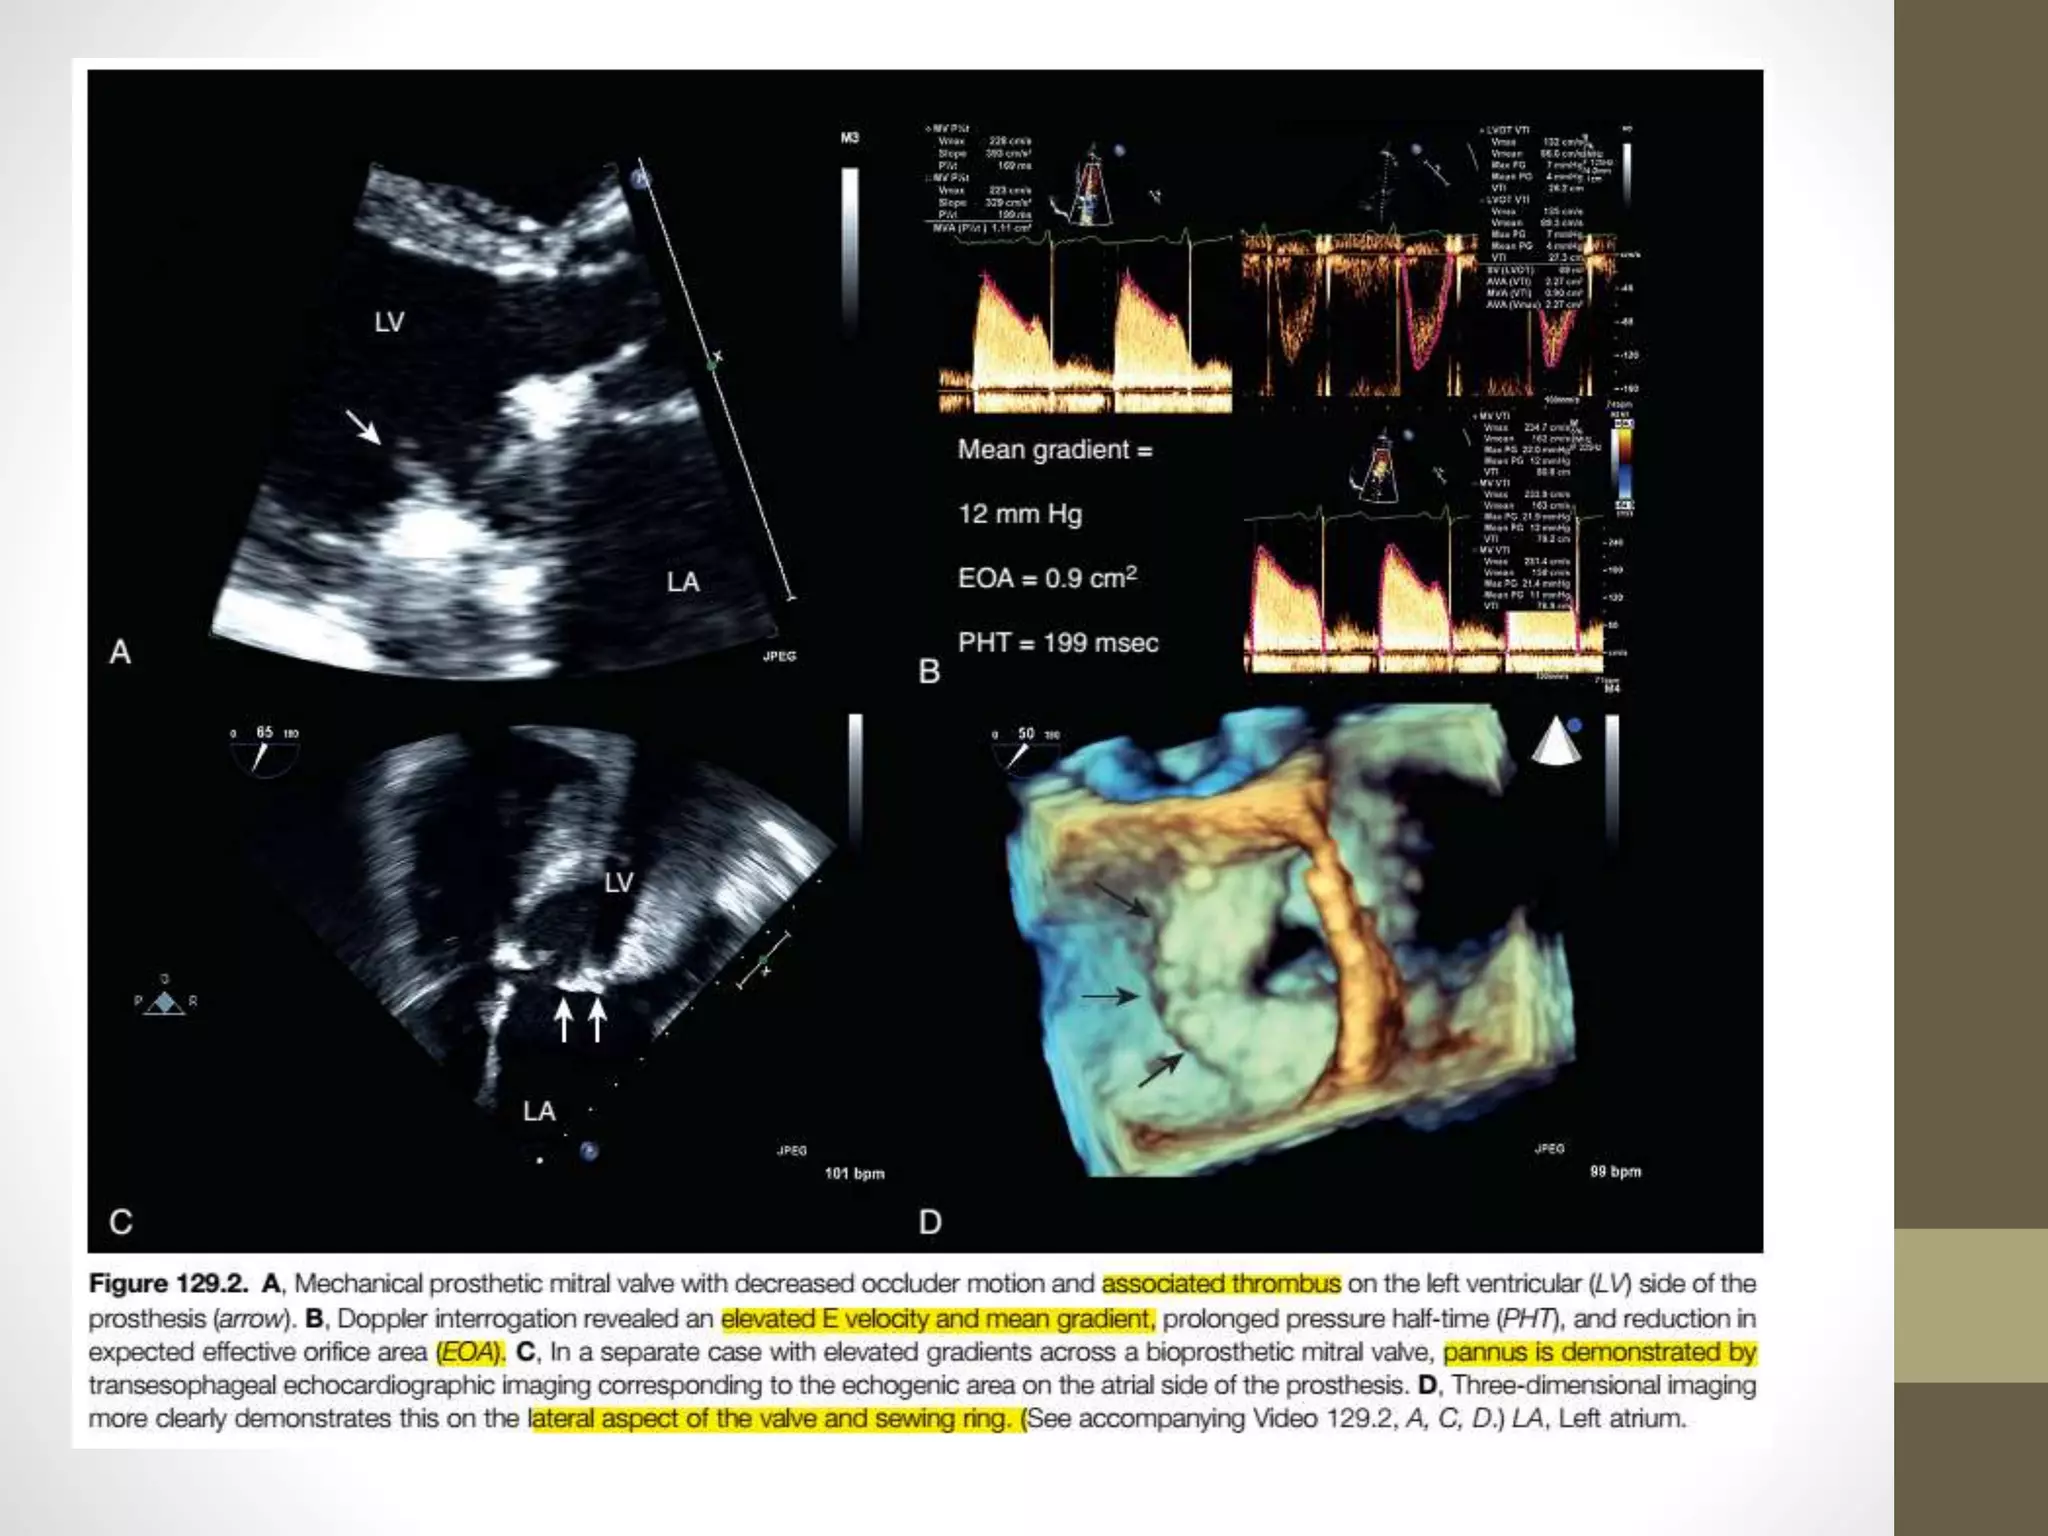

Prosthetic Valve Obstruction

• In mechanical valves, the usual causes of valve obstruction are thrombosis or

ingrowth of fibrous tissue called pannus below the inflow orifice of the valve,

restricting occluder motion.

• On Doppler examination, the hemodynamic diagnosis of valve obstruction is

suggested by

• (1) increased gradients for valve subtype and size,

• (2) decreased EOA below the normal reference range,

• (3) significant deviation of EOA from the baseline study,

• (4) increased PHT above the normal reference range, and

• (5) elevated DVI.

• Although individual EOA, PHT, and DVI values should always be referenced

against normal values for the valve subtype and size,

• an EOA less than 1.5 cm2, PHT greater than 150 msec and a DVI greater than

2.22 will almost always be abnormal and are useful numbers to memorize.

• Clinical suspicion of prosthetic valve thrombosis should be raised by symptoms of

heart failure, thromboembolism, or low cardiac output, coupled with a decrease in

the intensity of the valve closure sounds (mechanical valves), new and pathologic

murmurs, or documentation of inadequate anticoagulation

• Features favoring thrombus over pannus include “soft”

echogenicity and large size, together with clinical factors such

as short duration of symptoms and inadequate

anticoagulation.

• Mitral prosthesis occluder motion is well seen on TEE, making

CT or cine-fluoroscopy a rare requirement.